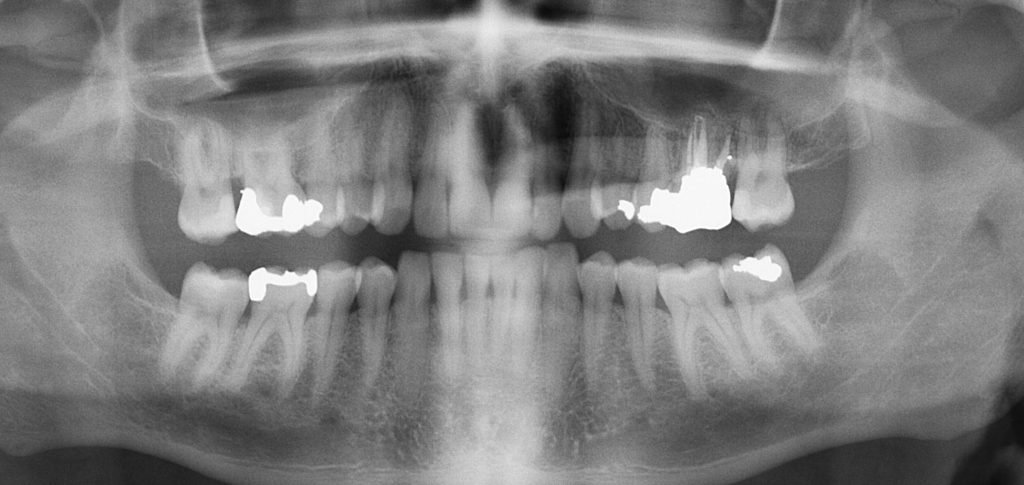

An OPG (Orthopantomogram) is a digital panoramic dental X-ray that provides a complete view of your upper and lower jaws, teeth, jaw joints, and surrounding structures in a single image. At our clinic, we use advanced OPG imaging to accurately assess impacted teeth, wisdom teeth, jaw alignment, infections, cysts, and bone health. This quick, painless, and low-radiation scan helps us diagnose conditions early and create precise treatment plans for braces, Invisalign, implants, and other dental procedures. Our clinic offers advanced OPG scan services, including digital orthopantomogram X-ray, panoramic dental X-ray, full mouth dental scan, and low-radiation dental imaging. We specialize in OPG for braces treatment, Invisalign planning, wisdom tooth assessment, impacted teeth diagnosis, jaw alignment evaluation, TMJ analysis, dental infection detection, cyst screening, and pre-implant assessment. If you are looking for an OPG scan near me, panoramic dental X-ray clinic, orthodontic X-ray services, or accurate dental imaging for treatment planning, our modern diagnostic technology ensures safe, quick, and precise results. We are one stop solution for all your dental problems. Together we make you smile. Consult us now. Contact us at 7259693009. Dentist near me, Best dental clinic in Bangalore, smile dental clinic, Orthodontic center Bangalore, Orthodontic center in BTM Jayanagar HSR, Top 10 dental clinic in Bangalore, Best dental clinic is BTM HSR Jayanagar, Invisalign, Invisalign clear aligners, Invisalign treatment, Invisalign treatment in Bangalore, Braces in Bangalore, Braces in BTM Jayanagar HSR, Invisalign in South of Bangalore.